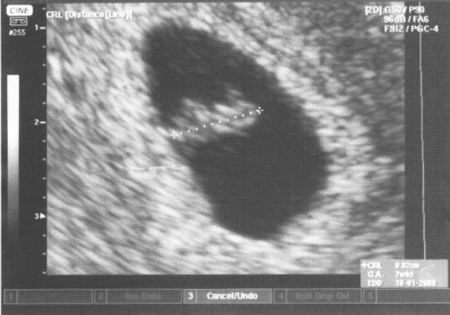

Zárodek v choriové dutině v 6. týdnu po oplození (8. týden těhotenství). Choriová dutina se jeví jako tmavá, na zárodku se dá dobře rozlišit hlavička a horní končetiny.

Zárodek v choriové dutině. Dá se dobře rozlišit výrazně dopředu ohnutý základ mozku, horní končetina s patrným loketním ohnutím. Od přední strany trupu odstupuje pupečník a připojuje se k placentě.

Autoři: Texty na základě zdroje www.babyonline.cz, vlastní praxe a znalostí zpracovala MUDr. Jarmila Halová, doplnil a upravil MUDr. Ondřej Šimetka, přednosta Porodnicko-gynekologické kliniky FN Ostrava, obrázky z UZ: MUDr. Radan Doubek, popis k nim: Doc. Šťastná. Poslední korekturu v srpnu 2024 provedla: MUDr. Veronika Ťápalová (Gynekologicko-porodnická klinika LF MU a FN Brno).